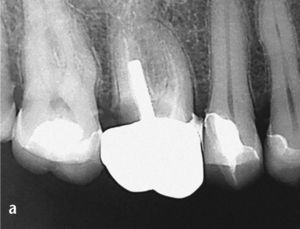

Los signos sugestivos de una determinada patogénesis son importantes para descartar las posibles causas de la enfermedad postendodóntica. No es raro que en dientes sin caries, que fueron endodonciados y que mostraban una periodontitis apical, persista la causa original de la enfermedad. En este tipo de dientes es importante bus-car variantes anatómicas como fisuras radiculares o una invaginación1,7 (figs. 1a y 1b). Las lesiones secundarias a traumatismos requieren una revisión exhaustiva de la región directamente afectada y de los antagonistas en el marco de la que se examinará la sensibilidad y se busca-rán microfisuras, fracturas y reabsorciones.

Se pasó por alto la puerta de entrada de una infección en un diente 12 sin caries a través de una invaginación. Vista desde palatino con displasias del esmalte en incisal y un agu-jero ciego con apertura ca-meral central (a). Radiografía con contraste del diente 12 para determinar la trayecto-ria de los conductos radicu-lares. Se desvitalizó el diente 11 en otro centro (b).